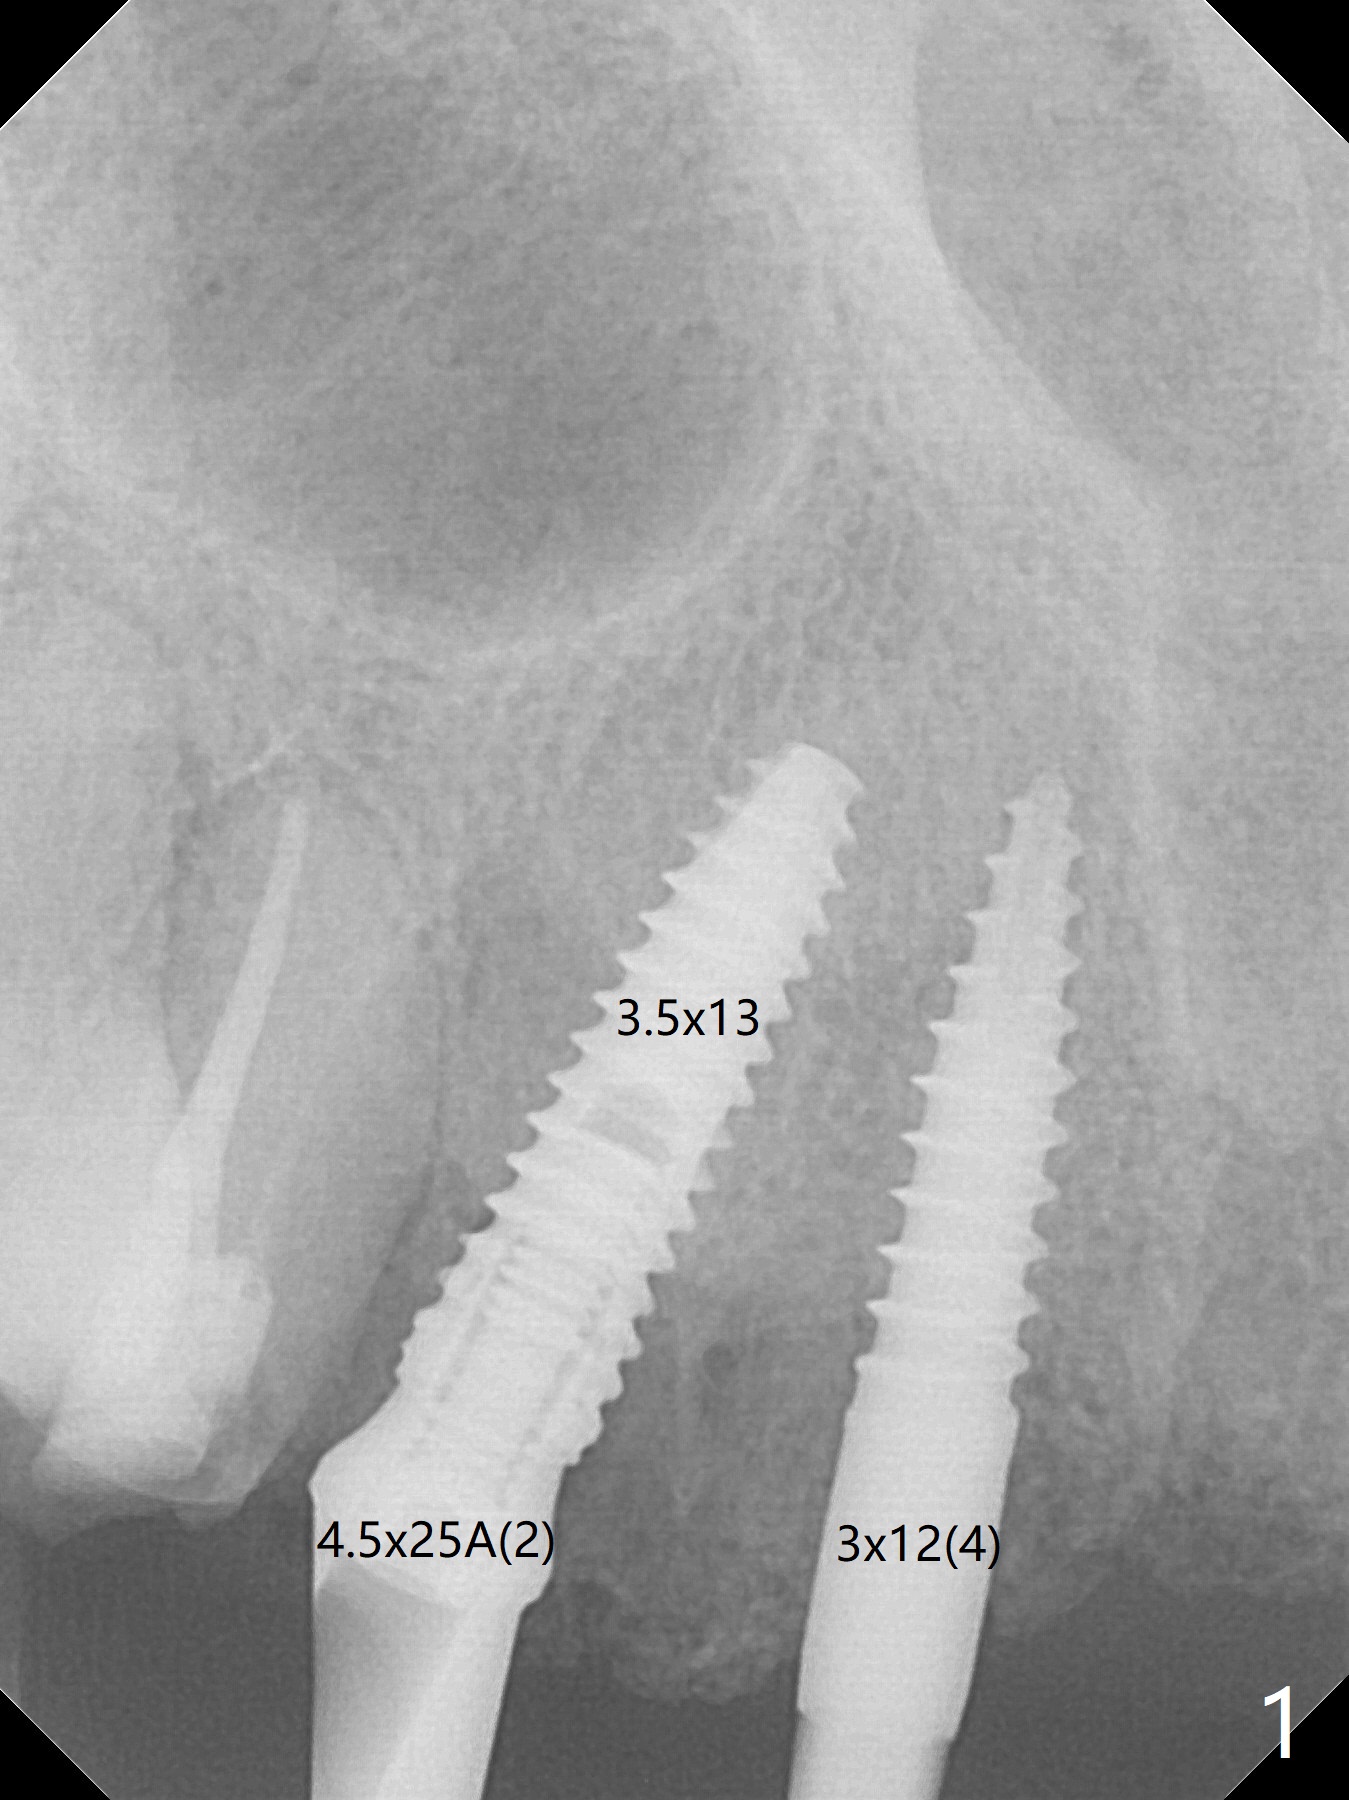

Restoration-Oriented Placement

It is smooth and quick to finish osteotomy with guide at #6,7,10-12, but when 3 mm 1-piece implants are placed free hand at #7 and 10 (Fig.1,2), the gingival parts of the abutments contact the incisal edges of the lower incisors (anterior deep bite) in spite of effort to change the trajectory by repeated back and forth placement after use of Lindamann bur buccally. Following an immediate provisional (Fig.3,4), the occlusal surface of the posterior teeth are raised to eliminate anterior restoration interference. Immediate postop CBCT shows that the implants at #7 and 10 could be placed more buccally (Fig.6,7, as compared to the normal position at #6,11,12 (Fig.5,8,9)). Fig.10 was taken 2 days preop, while Fig.11-13 postop. Can we change 1-piece implants (3mm) at #7 and 10 to 2-piece one (3.5) and use angled or cementation abutments for easy restoration (Fig.14-16)?